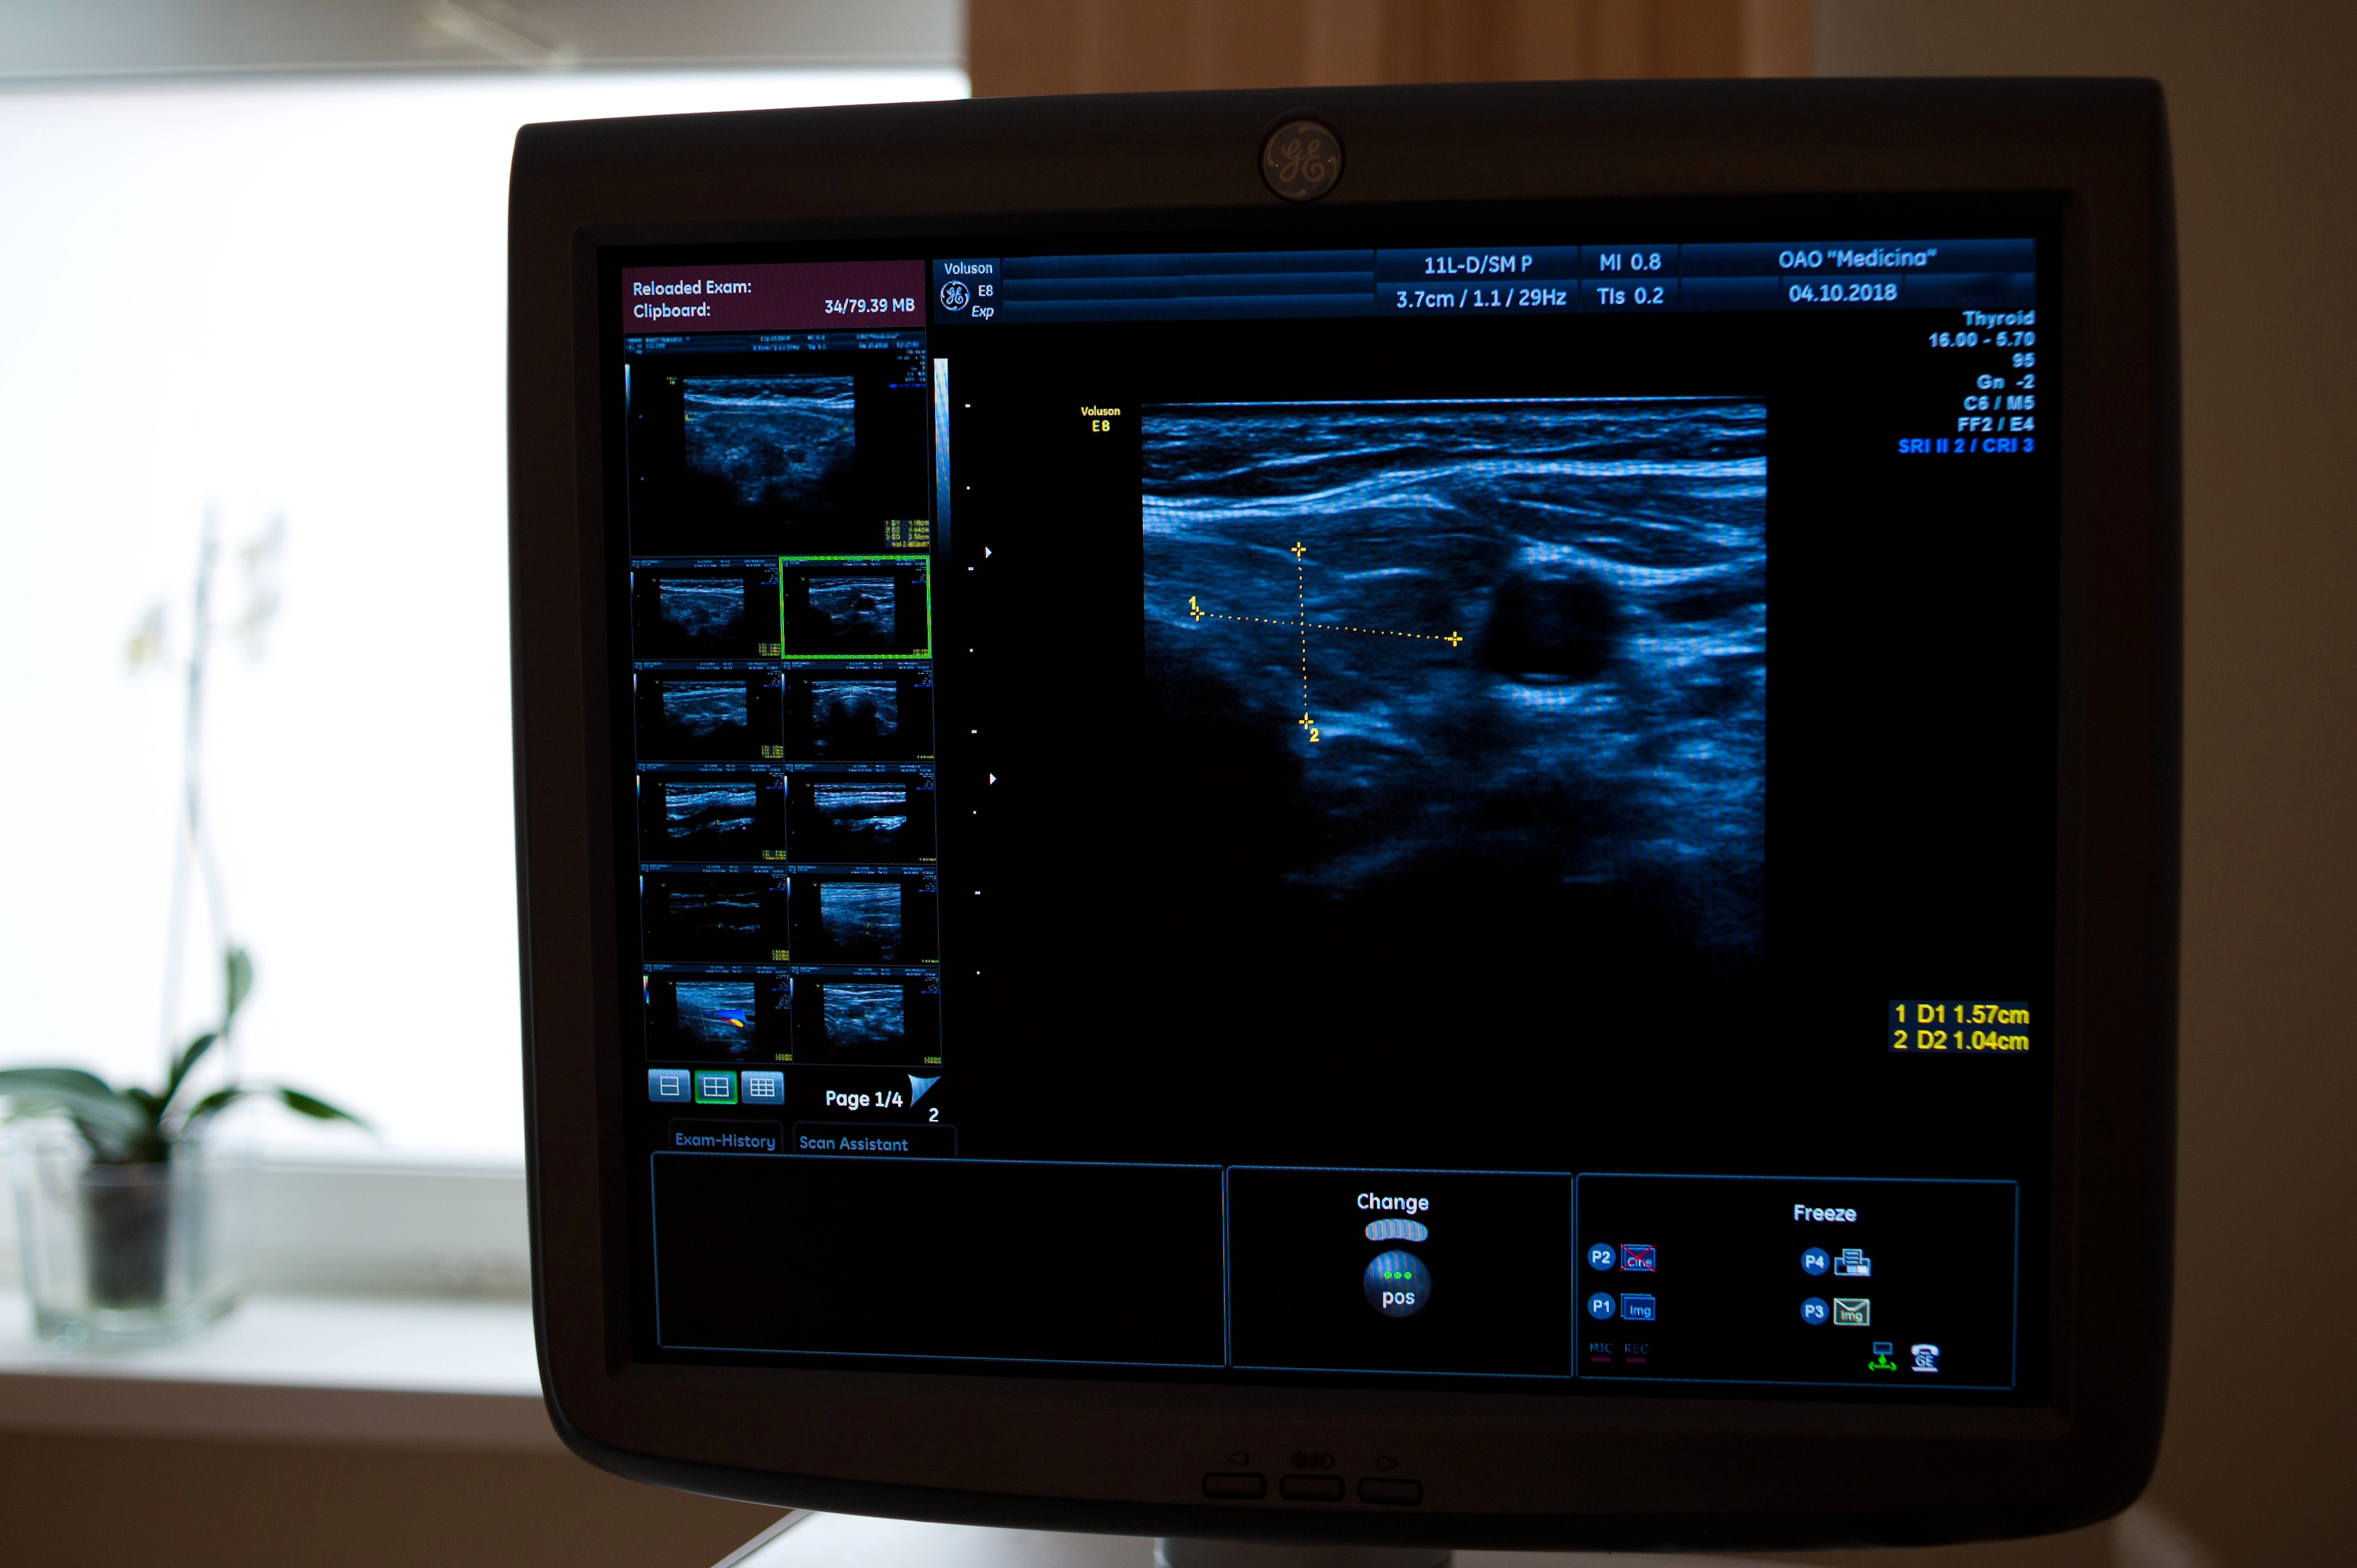

В нашей клинике в Москве Вы можете пройти процедуру УЗИ без ожиданий и очередей. Используемое нами оборудование обеспечивает максимальную точность результатов, что позволяет нашим специалистам ставить диагнозы даже в самых сложных случаях. Все исследования проводят профессионалы с большим опытом и стажировкой в крупнейших клиниках, в том числе зарубежных. Каждому пациенту мы предлагаем сопровождающего по клинике и личного врача-куратора, который будет вести больного до полного выздоровления.